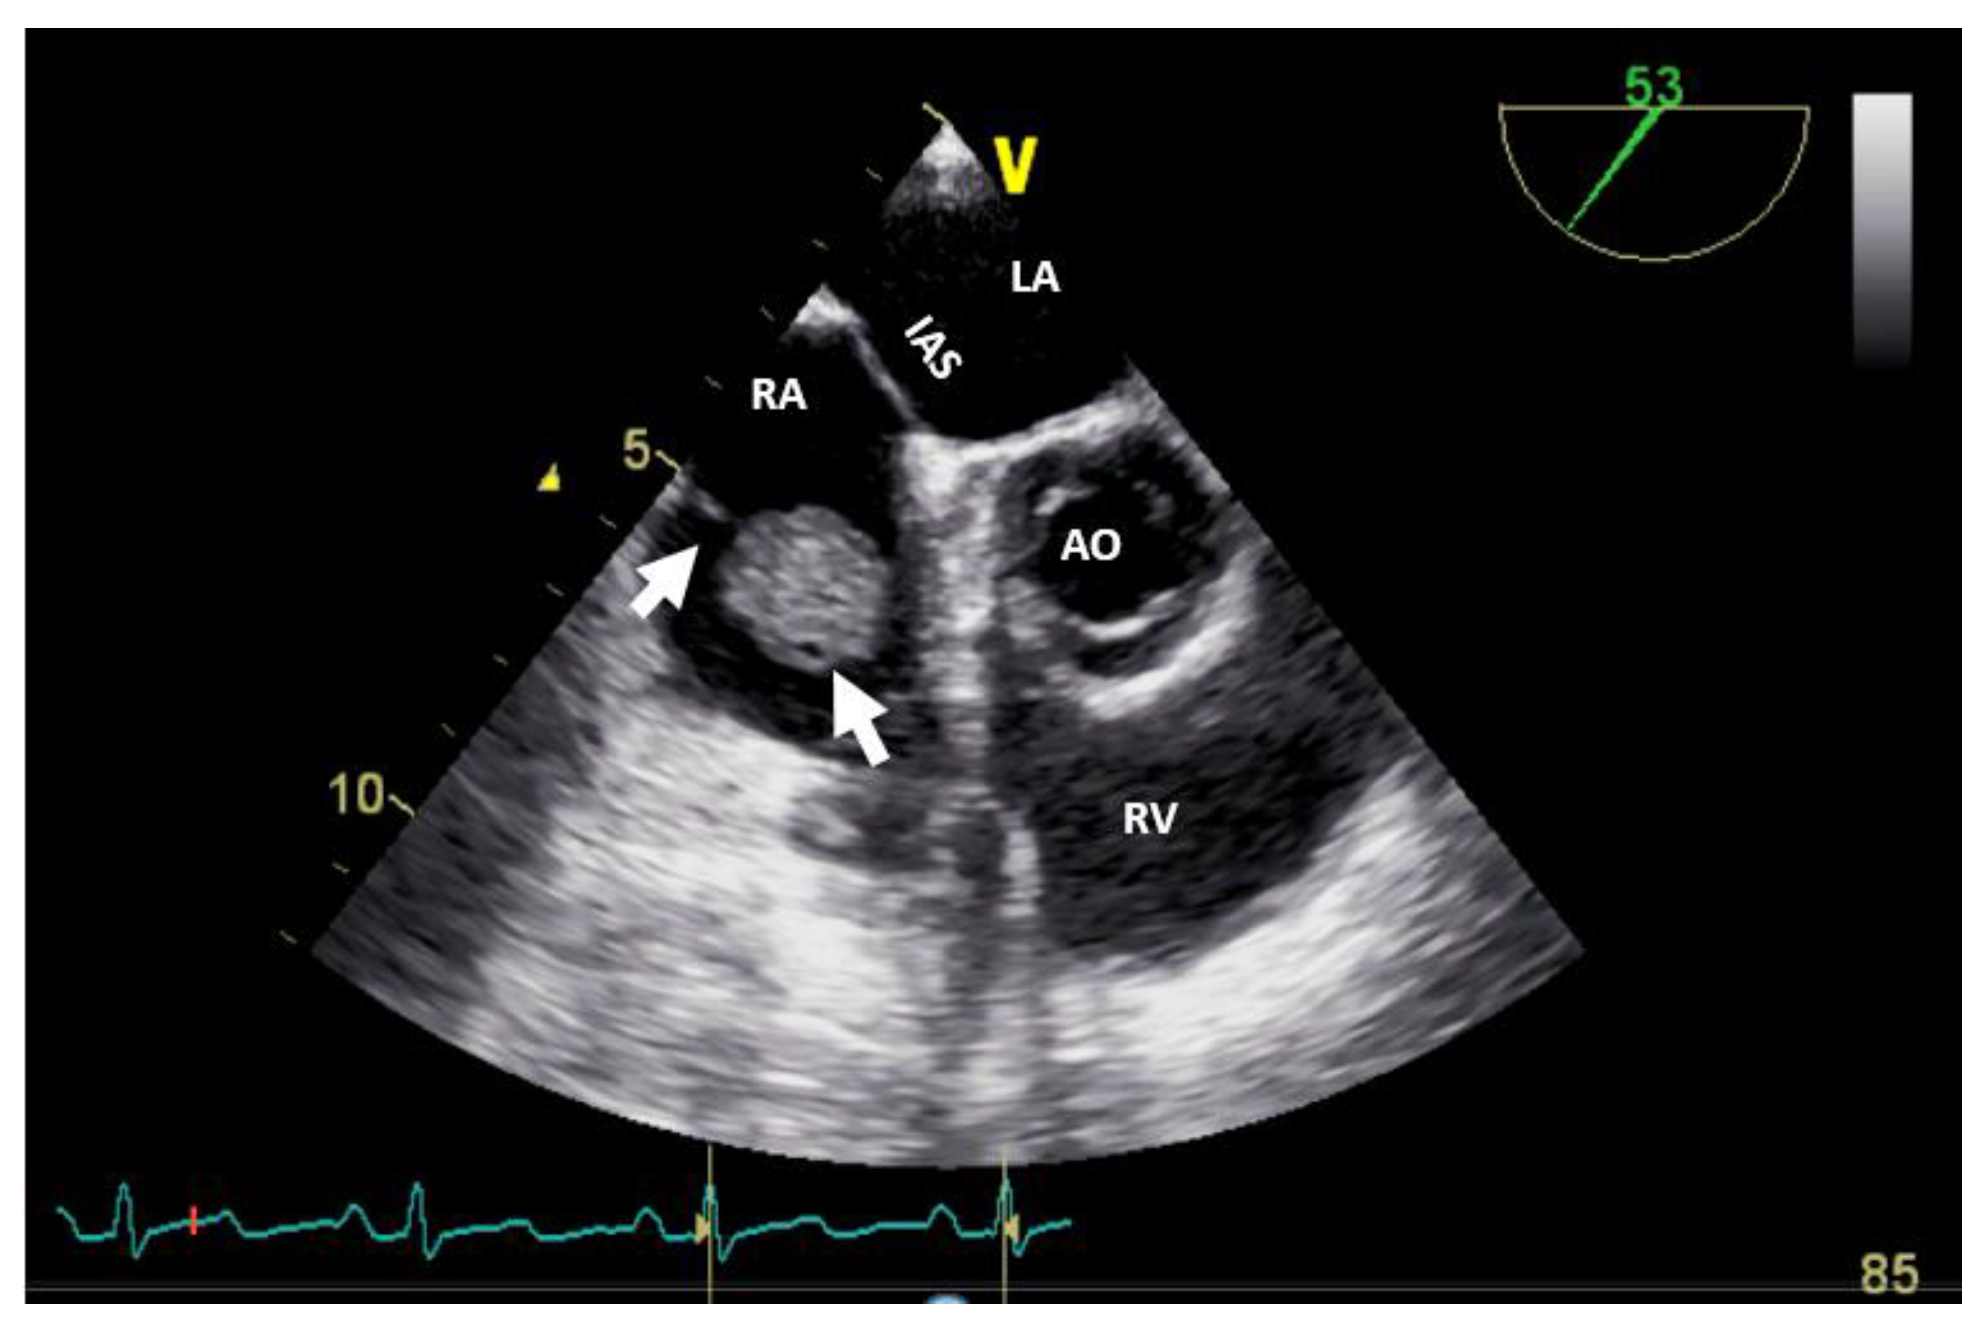

The echocardiography with ultrasound-enhancing agents is the best modality for tissue characterization [13]. Bi-dimensional TTE may sometimes overrate the size of myxomas or very soft tumors (myxoid or gelatinous type mass) due to his distensibility, mobility or irregular shape, especially when compared to three-dimensional TEE. However, most frequently, the size of the tumor is appropriately assessed by TTE. The site and the modality of tumor attachment, a useful clue to define the type of cardiac tumor, could be determined easily by TEE (especially 3D). For example, right atrium angiosarcomas, characterized by a heterogenic mass with central necrosis on CT or CMR [13], could be attached from any part of the right atrial wall, while myxoma (Figure 2) is usually situated in the fossa ovalis region of the atrial septum (most frequently on the left side).

Figure 2. Bi-dimensional transesophageal echocardiography (short axis view at the level of the great vessels) showing a huge masse, inhomogenous, attached to the interatrial septum crossing the tricuspid valve (which on histology diagnosis was a myxoma). AO, aorta; IAS, interatrial septum; LA, left atrium; RA, right atrium; RV, right ventricle.